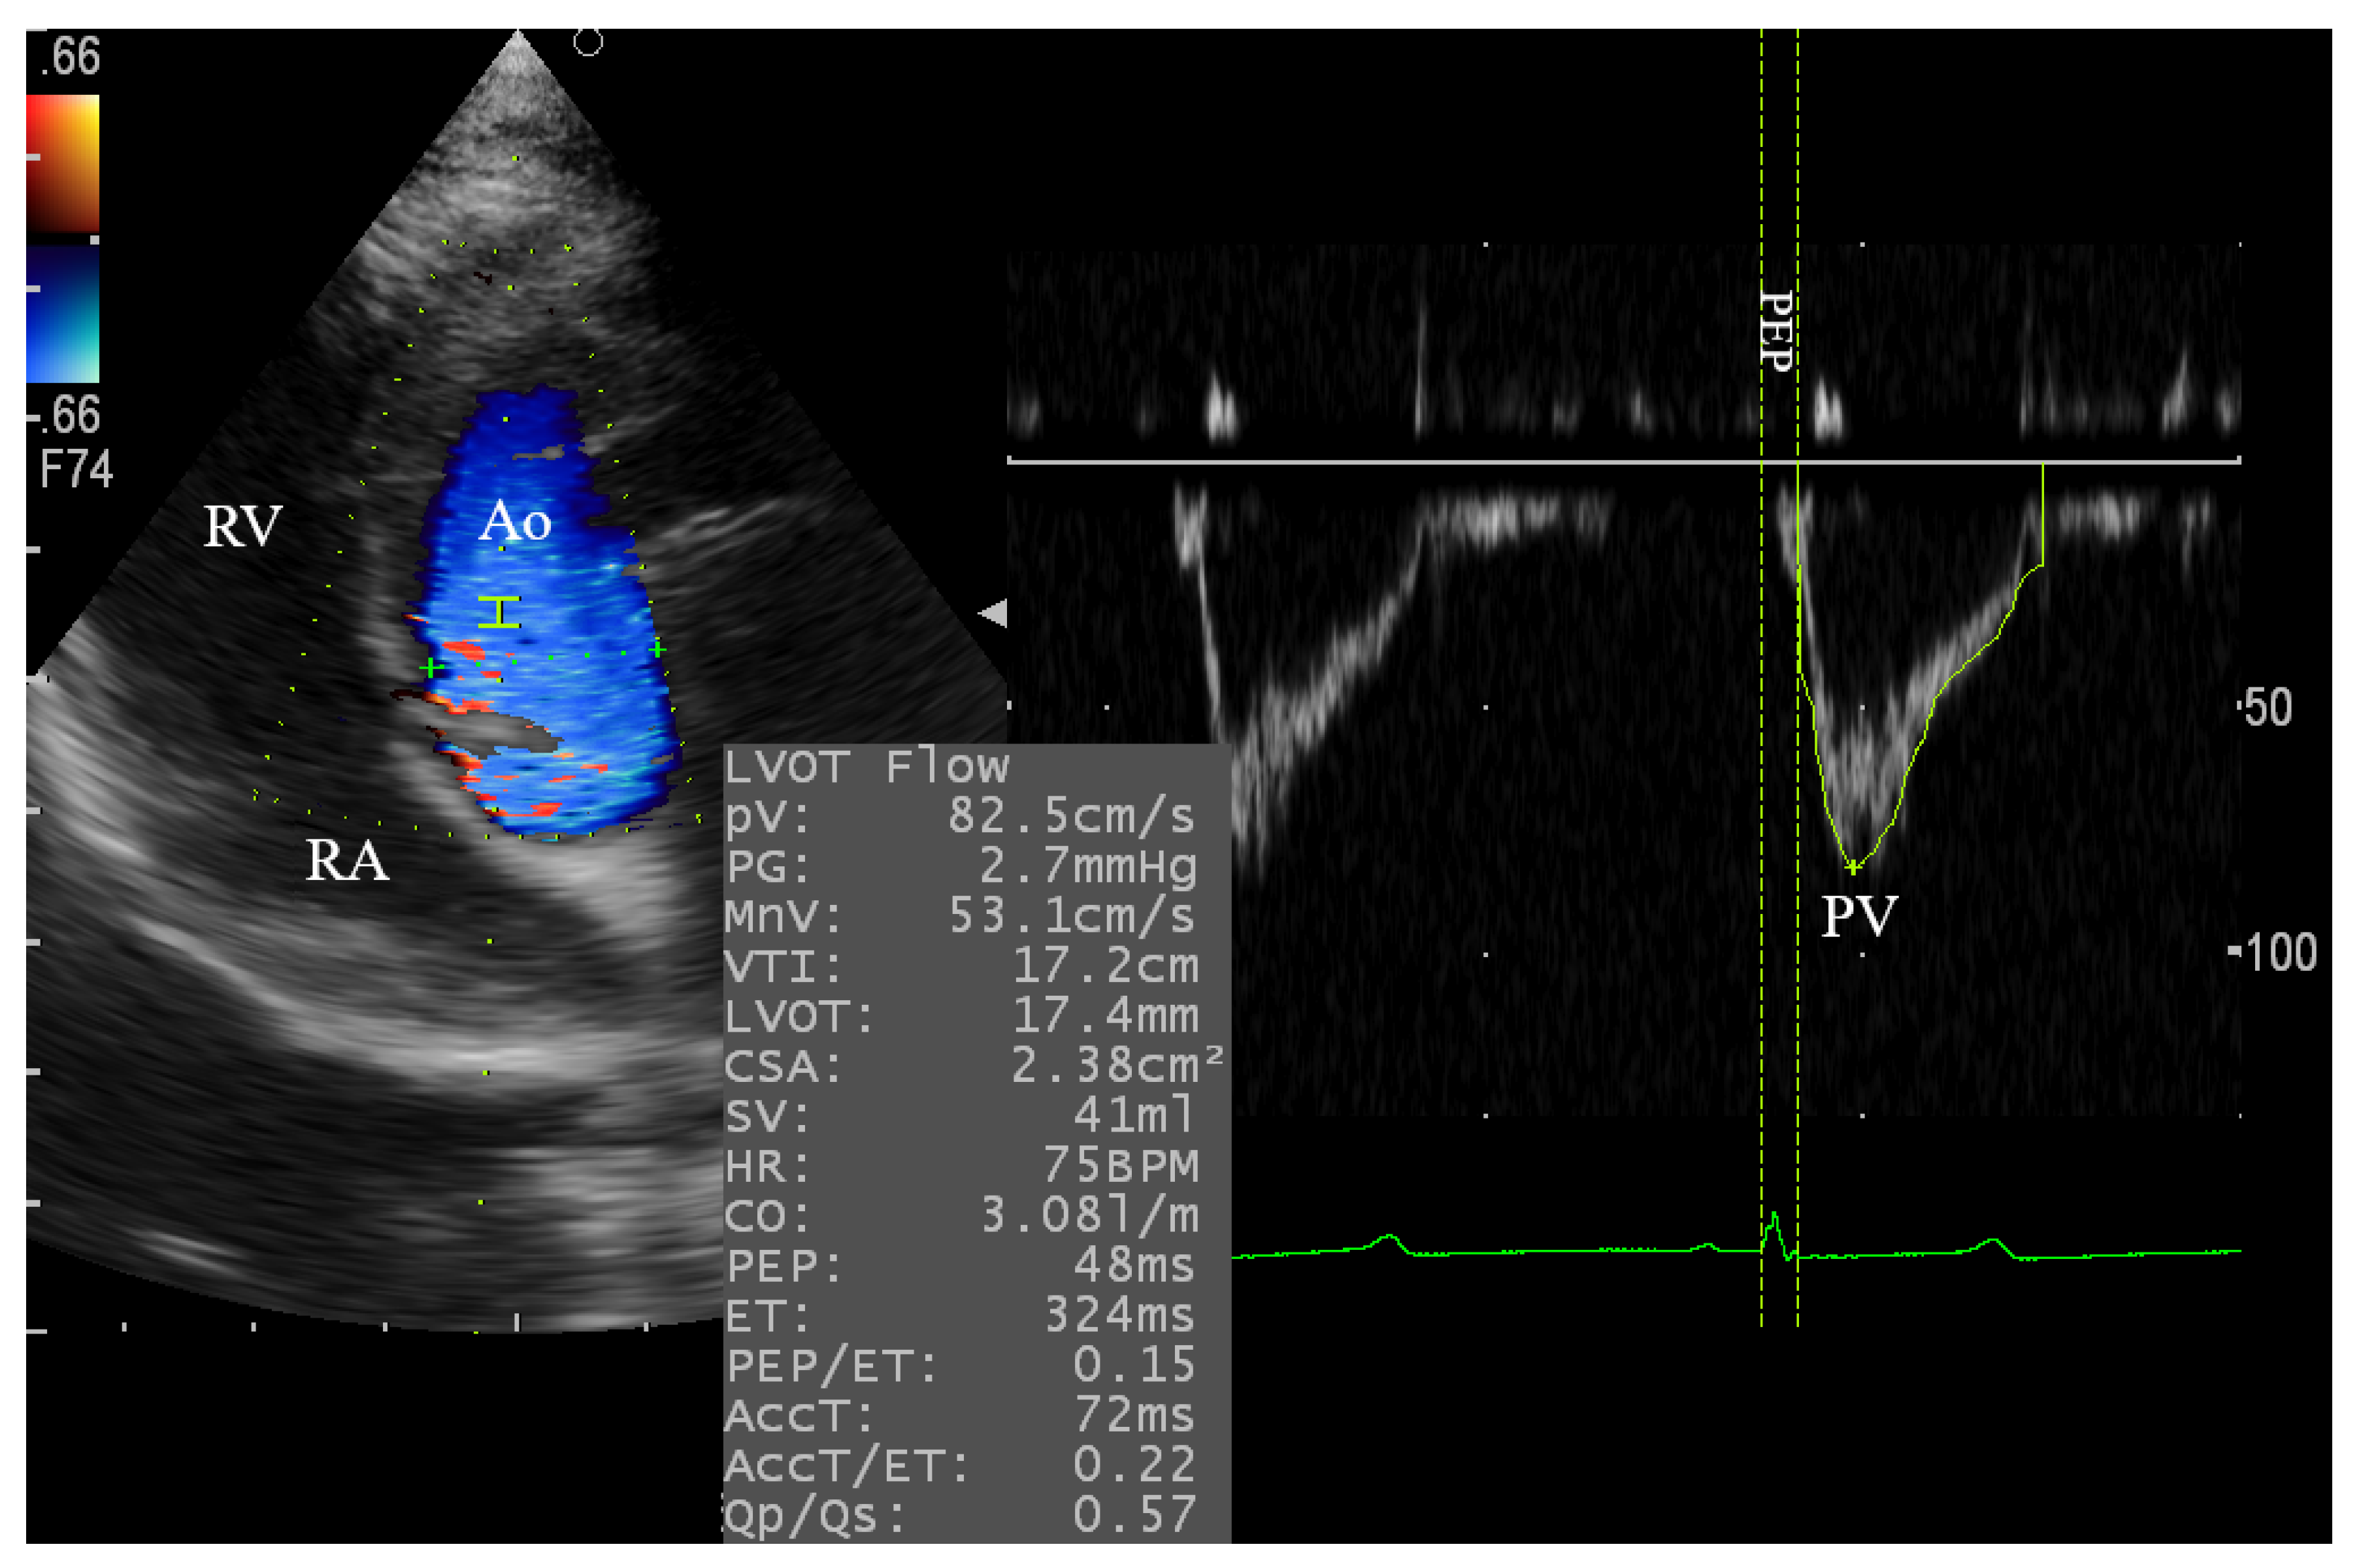

3.4.1. Assessment of the Aortic and Mitral Blood Flow

| Aortic | PV | cm/s | 81.75 | 10.62 | 0.064 | ns | 13.00 |

| PG # | mmHg | 2.781 | 0.757 | 0.006 | ** | 27.21 | |

| MnV | cm/s | 51.75 | 7.118 | >0.10 | ns | 13.75 | |

| VTI | cm | 12.42 | 2.558 | >0.10 | ns | 20.59 | |

| LVOT | mm | 16.22 | 2.552 | >0.10 | ns | 13.73 | |

| CSA | cm2 | 2.126 | 0.635 | >0.10 | ns | 29.86 | |

| SV | mL | 27.14 | 11.73 | >0.10 | ns | 39.81 | |

| HR | bpm | 106.8 | 18.19 | >0.10 | ns | 17.02 | |

| CO | L/m | 2.873 | 1.237 | >0.10 | ns | 39.05 | |

| PEP | ms | 38.86 | 10.98 | >0.10 | ns | 28.25 | |

| ET | ms | 240.2 | 41.22 | >0.10 | ns | 17.16 | |

| PEP/ET # | 0.167 | 0.072 | 0.005 | ** | 39.95 | ||

| ACCT | ms | 67.48 | 18.68 | >0.10 | ns | 27.69 | |

| ACCT/ET # | 0.282 | 0.082 | 0.044 | * | 29.09 | ||

| Aortic Doppler | ||||

| PV | cm/s | 93.1 ± 3.9 | 78.3 ± 1.5 | 0.01 * |

| PG # | mmHg | 3.4 ± 0.3 | 2.4 ± 0.1 | 0.00 * |

| MnV | cm/s | 55.9 ± 3.3 | 49.0 ± 0.8 | 0.05 |

| VTI | cm | 11.9 ± 0.8 | 14.5 ± 0.8 | 0.01 * |

| LVOT | cm | 13.8 ± 0.6 | 16.6 ± 0.4 | 0.02 * |

| CSA | cm2 | 1.5 ± 0.1 | 2.2 ± 0.1 | 0.01 * |

| SV | mL | 31.1 ± 2*1 | 30.7 ± 2.3 | 0.70 |

| HR | bpm | 128.5 ± 7.5 | 85.9 ± 6.3 | 0.01 * |

| CO | L/m | 3.8 ± 0.37 | 2.7 ± 0.2 | 0.02 * |

| PEP | ms | 35.3 ± 4.8 | 45.4 ± 3.3 | 0.11 |

| ET | ms | 216.0 ± 16.9 | 294.8 ± 15.7 | 0.00 * |

| PEP/ET # | 0.20 ± 0.0 | 0.20 ± 0.0 | 0.81 | |

| ACCT | cm/s | 56.7 ± 6.1 | 72.4 ± 3.9 | 0.02 * |

| ACCT/ET # | 0.25 ± 0.0 | 0.25 ± 0.0 | 0.81 | |